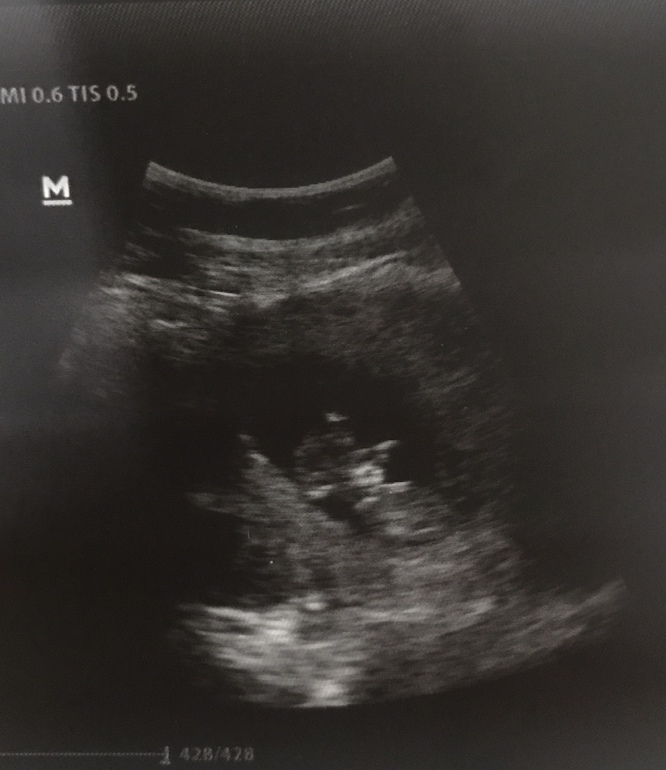

11 недель

Сегодня сдала НИПТ на 12 хромосом , бонусом будет определение пола. Сказать, что я волнуюсь , это ничего не сказать. Целый день пытаюсь отгонять от себя мысли о плохом. Все же надо успокоиться и верить в то, что все у нас хорошо. Перед анализом съездила к своему врачу на контроль сб . Она смотрела , улыбалась и сказала, что все у нас чудесно , все по срокам.

Моя козявка сидит, ручками уже машет. Кем бы ты ни была моя лялечка , такая долгожданная и такая нужная нам всем, мальчиком или же девочкой , просто будь здоровой моя крошечка 🙏🏻